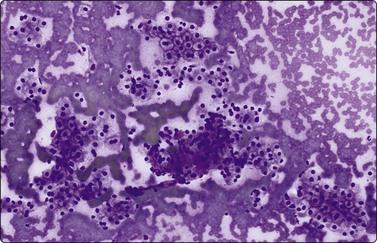

Hepatoblastoma177-181

Hepatoblastoma is a rare, highly malignant tumor of infants and young children, which metastasizes early. It is not associated with chronic liver disease. The alpha fetoprotein level is significantly raised in approximately 90% of cases. Patients can have a good response to surgery and chemotherapy. There is a spectrum of subtypes from anaplastic through embryonal and fetal to macrotrabecular, based on growth pattern and increasing resemblance of component cells from anaplastic towards hepatocyte morphology. A mixed epithelial and mesenchymal pattern includes primitive mesenchyme. The cytological appearance is that of a small round cell childhood tumor, (Fig. 10.28, and also Figs 17.1817.20), with clusters, ribbons and rosettes of embryonal cells, which are small cells with a high N : C ratio, oval to spindled nuclei, coarse chromatin, prominent, often multiple, nucleoli, and scant to moderate cytoplasm. Fetal epithelial cells, are slightly smaller than hepatocytes with round regular nuclei, fine chromatin, prominent central nucleoli and abundant granular or clear cytoplasm which may contain fat, bile or glycogen. Fragments of mesenchyme may be observed. Foci of extramedullary hemopoiesis are often present. The differential diagnosis is that of other small round cell childhood tumors metastatic to the liver or of HCC, which may occur in older children. HepPar-1 staining of hepatoblastoma can be useful in this regard.182

Fig. 10.28 Hepatoblastoma

Tumor tissue fragment, showing nuclear crowding and overlapping, increased nucleocytoplasmic ratios, irregular chromatin, minimal cytoplasm (MGG, HP).